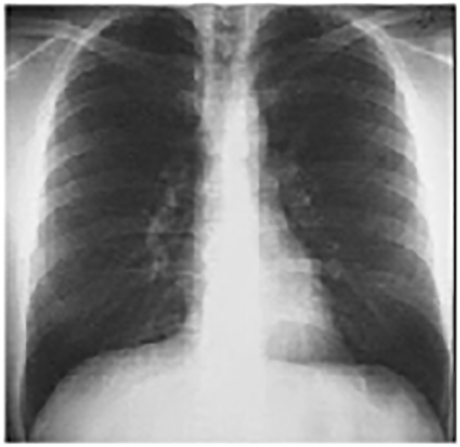

For teaching purposes, the following PA chest X ray from another patient is presented.